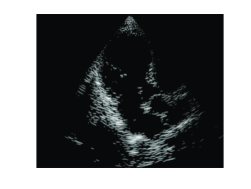

Applying an IDFT on , we obtain the beamformed signal. We can now proceed to standard image generation steps which include log-compression and interpolation. To demonstrate the equivalence of beamforming in time and frequency, we applied both methods on in vivo cardiac data obtained as explained in Section 2, yielding the images shown in Fig. 2. As can be seen, both images are identical.

(a)

(b)

The synthesis approach has a significant drawback. The assumption of a small number of reflecting elements , forces us to treat only the strong reflectors located in direction . In such a setup we essentially loose all the weak reflectors that appear as speckle, namely, granular pattern that can be seen in Fig. 2, and carry important information in medical imaging.

To demonstrate the proposed method, a subset of Fourier coefficients corresponding to the central frequency samples in the bandwidth of the transmitted pulse were chosen. To calculate we need at most samples per individual signal, implying 25 fold reduction in sampling rate. The result is shown in Fig. 5 (a). To compare the proposed solution with the previously developed OMP based method [6], the same subset was used to reconstruct the beamformed signal assuming strong reflectors in each direction . The resulting image is shown in Fig. 5 (b).